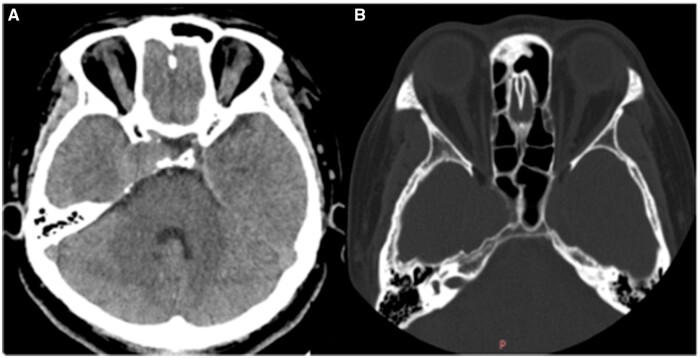

Generally, due to the complexity of the skull base structures, it is difficult to differentiate cavernous vascular malformation and meningioma in the cavernous sinus area using conventional imaging studies. Cavernous sinus venous malformation are characterized by increased capillary masses without a direct arterial supply, typically leading to low perfusion. On the other hand, meningiomas receive arterial blood supply to the tumour and often exhibit high perfusion. So, arterial spin labelling (ASL) can be helpful in distinguishing between the 2 tumour types. However, in our specific case of a cavernous sinus venous malformation, the ASL imaging showed hyperperfusion. Further analysis revealed that this hyperperfusion on ASL can occur when cavernous sinus venous malformation is associated with arteriovenous fistula malformation.